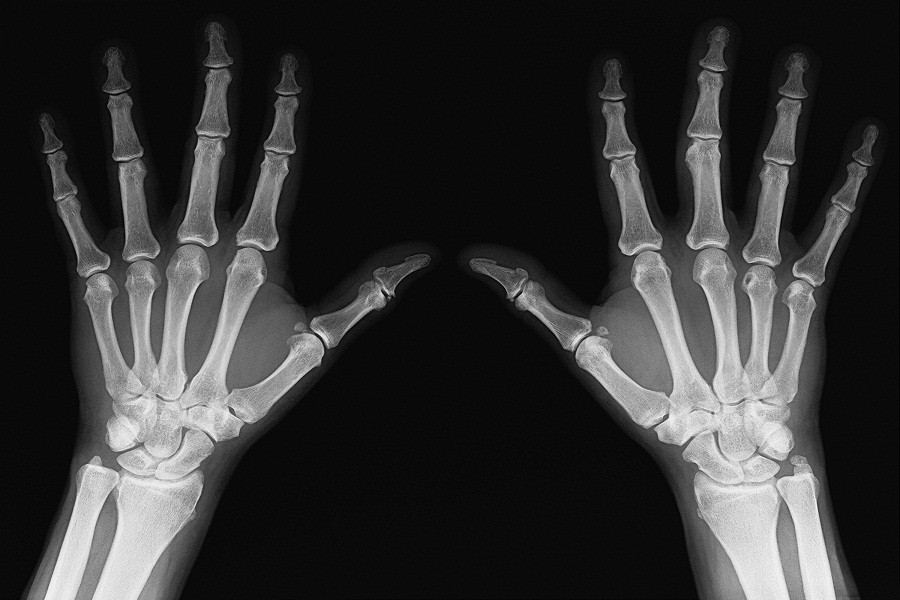

এটি একটি বিরল ধরনের রোগ যা ফিব্রোডিসপ্ল্যাসিয়া অসিফিক্যানস প্রোগ্রেসিভা বা স্টোনম্যান সিনড্রোম হিসেবে পরিচিত। এটি একটি জেনেটিক ডিজঅর্ডার। এর ফলে হাত ও পায়ের একটোপিক সফট টিস্যুগুলো আক্রান্ত হয় এবং দেহের কানেকটিভ টিস্যু, মাসল টিস্যু, লিগামেন্ট ও টেনডনসগুলো ধীরে ধীরে হাড়ে পরিণত হতে শুরু করে।

একসময় শরীরের যে কাঠামো বা কংকাল রয়েছে তার বাইরে দিয়ে হাড়ের পুরু আস্তর জমা হয় ফলে মানুষ একদম চলাফেরা করতে পারে না এমনকি খাওয়াদাওয়া বা কথা বলাও অসম্ভব হয়ে পড়ে। পরিস্থিতি আরও ভয়াবহ হয়ে উঠে যখন বুকের পাঁজরের চারপাশে বাড়তি হাড় জমে ফুসফুসের জায়গা সংকুচিত হয়ে যায়। এই কারণে একজন আক্রান্ত রোগীর নিঃশ্বাস নিতেও কষ্ট হয়।

এর শুরুটা হয় ঘাড় বা কাঁধ থেকে এবং ধীরে ধীরে তা শরীরের নীচের অংশে ছড়িয়ে পড়ে। তবে শরীরের যেকোনো অংশ, যেমন-পাঁজর, শ্রোণিদেশ, মাথার খুলি, ফিমার বা হিউমেরাস যেকোনো জায়গাতেই এই সিনড্রোম দেখা দিতে পারে। এই রোগটি যতটা না অদ্ভুত তারচেয়েও বেশি ভয়াবহ!